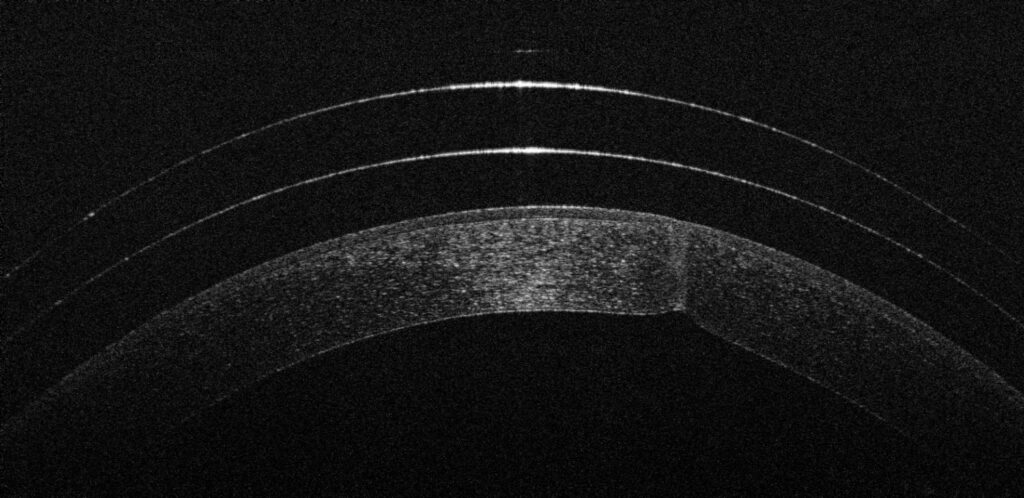

Tras un estudio exhaustivo de la superficie de su ojo, optamos por la adaptación de una lente escleral.

¿Por qué escleral? Porque este tipo de lentes no toca la zona dañada de la córnea. En su lugar, se apoya en la parte blanca del ojo (la esclera) y crea una nueva superficie óptica perfecta sobre la cicatriz, bañada constantemente en suero fisiológico.